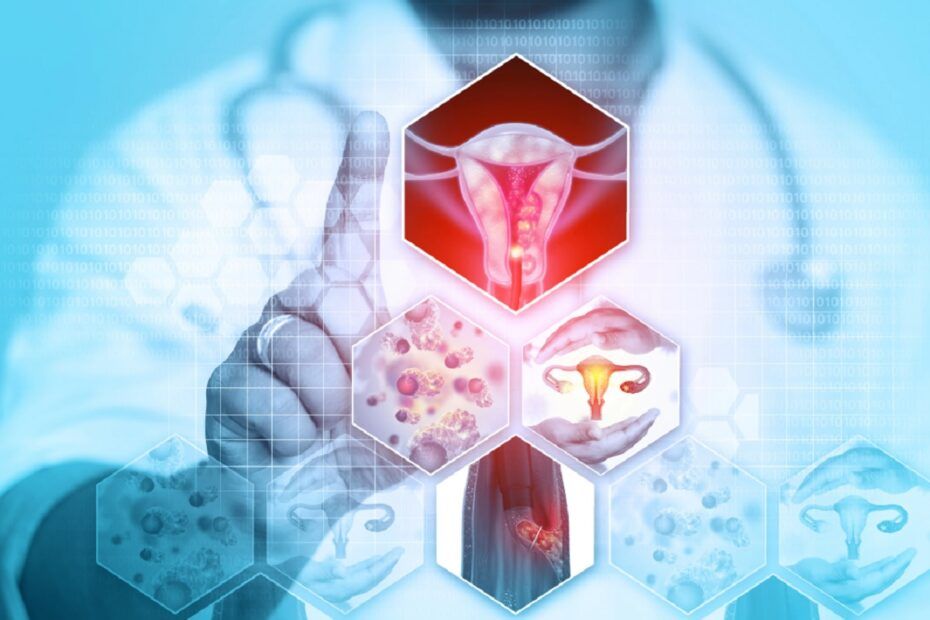

Cancerul este boala care are ca mecanism o proliferare celulara anarhica, necontrolata si neintrerupta. Se mentioneaza, in Europa si in America de Nord, predominanta cancerelor de plaman, atribuibile in proportie de 90% tabagismului, a cancerelor colorectale, legate, probabil, in parte de alimentatie, si a cancerelor de san, cu cauze inca putin clare. In Africa se evidentiaza frecventa cancerelor de ficat in zonele endemice pentru hepatita B si cea a cancerelor de col uterin in tarile in care natalitatea este ridicata si unde inca igiena este defectuoasa, ceea ce are drept consecinta un nivel ridicat al bolilor transmisibile sexual (papiloma sau herpes), care pot sta la originea acestor cancere.